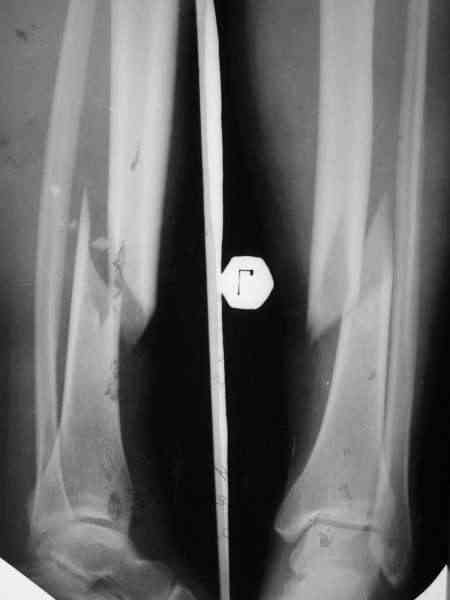

Типичный косо-спиральный перелом голени с низкой энергией, большеберцовая внизу, а сверху малоберцовая, и применение интрафрагментарного компрессионного шурупа можно оправдать, когда для

фиксации перелома выбран метод открытой фиксации пластинами, где пластина после стабилизации и компрессии перелома действует как нейтрализующая сила.

Без установки межфрагментарного шурупа, предпочителями отечественного метода Илизарова, дежурным аппаратом из двух колец при поступлении в приемном покое и на следуюший день двумя дополнительными спицами с напайкой за пределы фокуса решили бы проблему в два счета.

Такие изолированные (low energy trauma) переломы голени лечатся также гипсом, поэтапным консервативным методом Sarmiento, поэтому трудно согласиться с принятии метода, дать ему "право на жизнь" как стандарта для лечении при изолированных переломов голени.